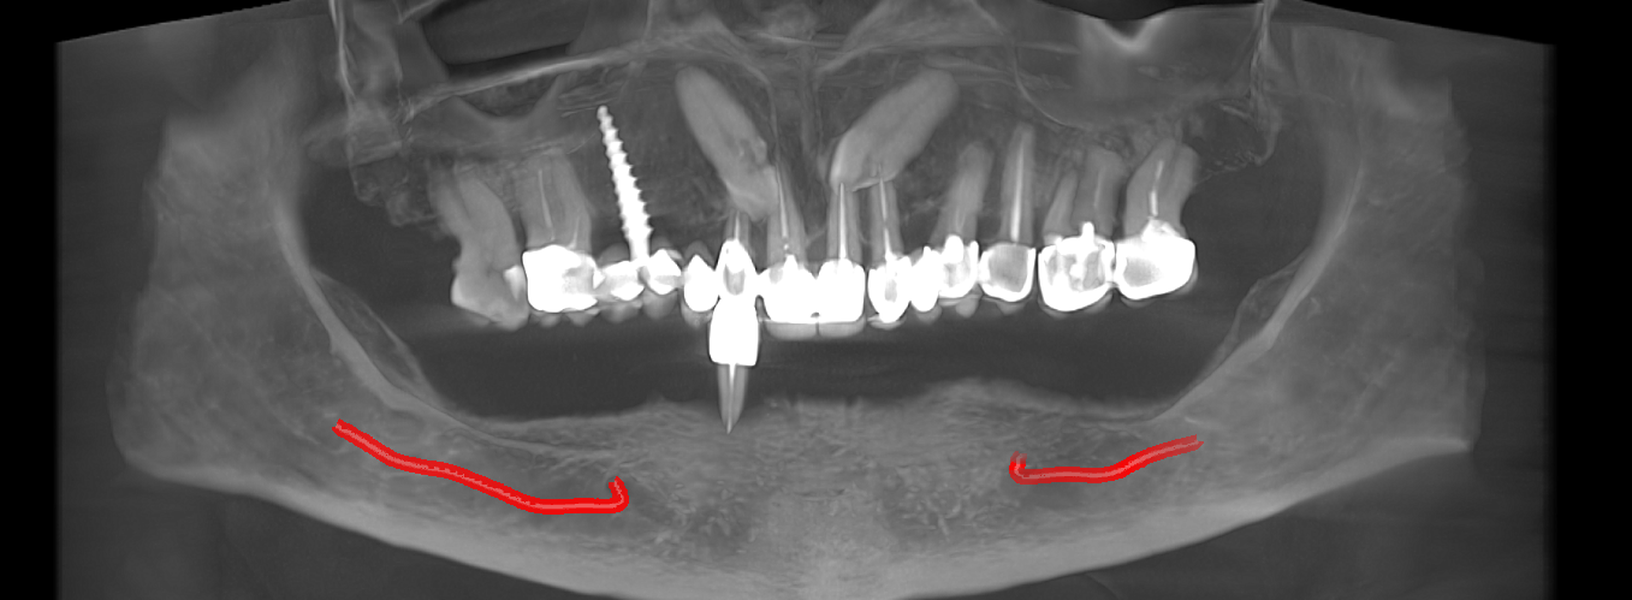

studii științifice.În cazurile de atrofie osoasă severă, când inserarea implanturilor în zonele laterale nu este posibilă fără adăugare osoasă, conceptul All-on-4 prevede plasarea implanturilor în unghiuri strategice pentru a evita zonele deficitare. Astfel, două implanturi sunt plasate în zona incisivilor laterali, iar alte două în zona premolarilor.

Tomografii (CBCT)

Caz 2